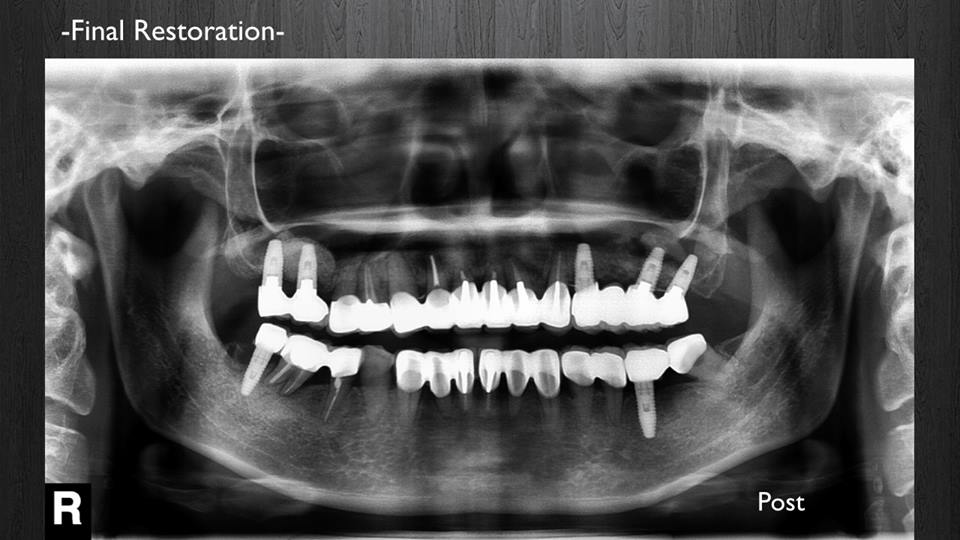

< 症例2 >

- 治療期間:28ヶ月

- 治療回数:145回

- 治療歯数:28歯

- 費用:全顎矯正治療80万円 インプラント治療:195万円 上部セラミック:300万円

- リスク:メンテナンスを怠ると、インプラント周囲炎になる可能性があります。

- インプラント手術には合併症が伴う場合があります。

- 治療期間は治癒の状態により前後する場合があります。